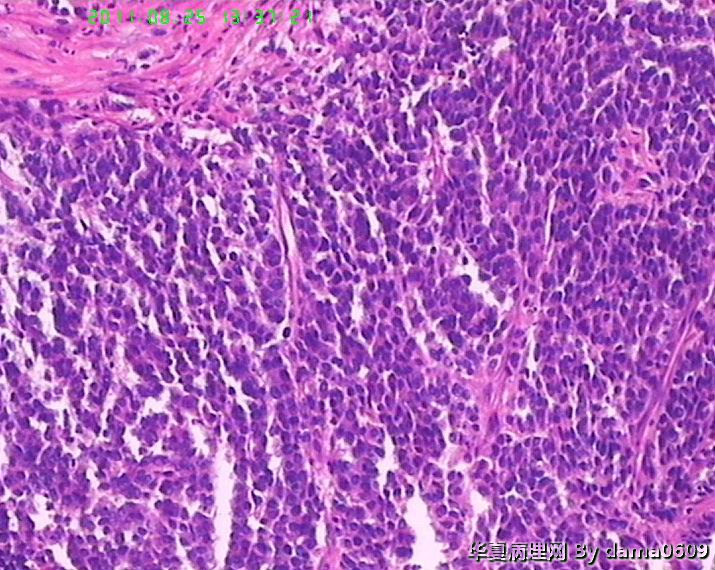

患者男性,39岁。以回盲部肿物行肠镜检查、活检。镜下四块组织内有两块见呈巢状的小细胞(如图

),另两块为粘膜慢性炎表现及坏死组织。学生不知如何分类:未分化癌?类癌?小细胞癌?请老师指教。谢谢!

细胞核较小、深染、一致,核分裂象少见,支持典型类癌。

神经内分泌肿瘤 淋巴瘤 低分化腺癌。。。

楼主是想说“未分化癌”?片子切的比较厚,考虑神经内分泌肿瘤,低分化腺癌待排。